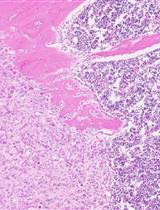

• The Ad-Cre-Luc-mediated ablation of Pten leads to hyperplasia that progresses through prostatic intraepithelial neoplasia (PIN) to adenocarcinoma.

A milestone in this field is the creation of the prostate-specific Pten conditional knockout (cKO) mouse model, which closely mimics the formation and growth of human PCa and has become an established PCa preclinical model [4]. However, as Pten deletion in this model is an automatic process triggered in very young prostate tissue (less than eight weeks old), it is challenging to mimic the physiology and the microenvironment (old prostate tissue) in which human PCa develops. We created a novel mouse model where Pten KO can be spatially and temporally controlled (Pten adcre+) using a virus-assisted in vivo cKO approach. The prostate-specific Cre-LoxP gene switching was generated via intraductal delivery of adenovirus to the anterior prostate lobes [5]. Adenovirus is a DNA virus that does not integrate into the host genome. It infects dividing and nondividing cells, leading to a transient high-level protein expression [6]. Using the intraductal delivery method, we obtained epithelial-specific prostate infection with Cre-expressing adenoviruses, leading to the deletion of the floxed Pten gene in the prostate epithelium.